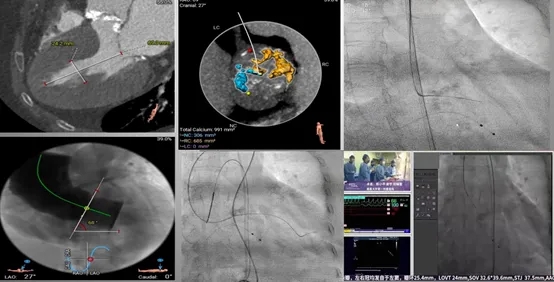

横位心、重钙化TAVR

重度狭窄、钙化、高低瓣,跨瓣困难,快速起搏后增加跨瓣机会